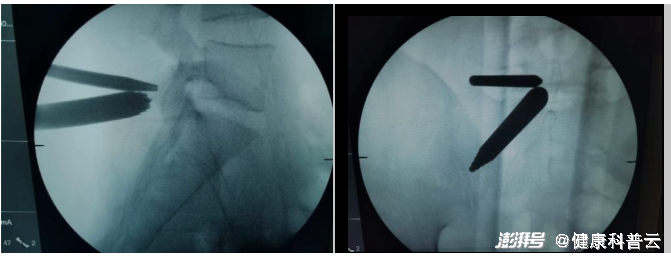

术中操作

手术切口